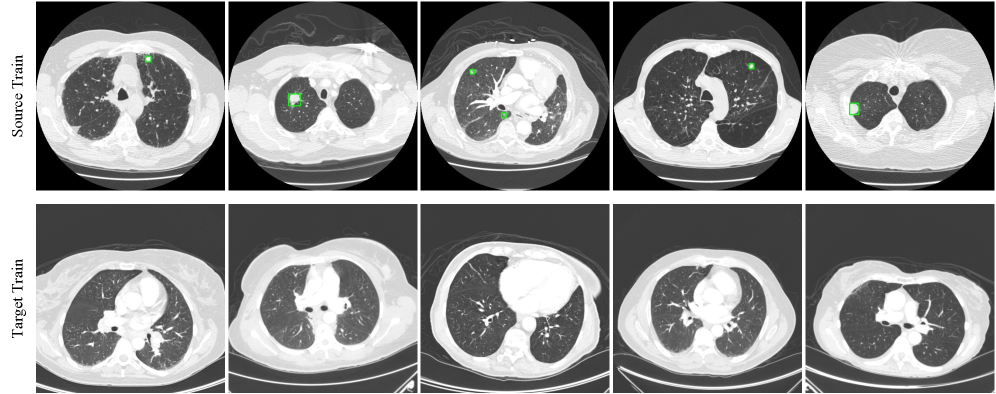

Refer to caption

Figure 4: Examples of the three benchmarks. The IF-CARLA benchmark illustrates a domain shift from daytime to nighttime driving scenes. The IF-CCT benchmark captures a modality shift between visible-light imagery and infrared illumination. The IF-LUNA16 benchmark represents a cross-device transfer scenario, where differences in image layout, noise characteristics, and CT reconstruction protocols create inter-device domain discrepancies. Objects are marked with green bounding boxes.

We propose three dedicated benchmarks to facilitate research in the challenging instance-free scenario. Figure 4 illustrates sample images, while detailed statistics information is available in the appendix.

Lung Nodule Detection. In clinical practice, a number of labeled nodule cases are often available for an established CT scanner, whereas a newly deployed scanner typically lacks labeled positive samples. Acquiring sufficient positive data on the new device is slow and costly. Pulmonary nodules are relatively rare in the screening population, and even in nodule-positive scans, nodules occupy only a small fraction of slices, while most slices are nodule-free. This naturally aligns with the Instance-Free DAOD scenario. LUNA16 dataset (Setio et al., 2017) is a public benchmark in medical image analysis for lung nodule detection. It is a standardized subset of the LIDC-IDRI database (Armato III et al., 2011), which consists of numerous chest CT scans with nodule locations annotated by multiple radiologists. The LUNA16 dataset originates from CT scanners of different manufacturers, such as GE and Philips. Due to different scanners, reconstruction algorithms, and scanning parameters like layer thickness and X-ray dosage, the resulting images exhibit different layouts, textures, noise levels, and image contrast.

We use 2,008 CT slices containing lung nodules from GE scanners as the source-domain training set. For the target domain, we use 865 nodule-free CT slices from Philips scanners as the target domain training set, and 231 Philips slices containing nodules as the target domain validation set, named the IF-LUNA16 benchmark.

We established three dedicated benchmarks covering driving simulation, ecological monitoring, and medical diagnosis. Specifically, the IF-CARLA benchmark offers a simulated autonomous driving scenario with a day-to-night domain shift. It provides a strictly controlled environment with precise annotations, serving as a reliable foundation to support future research. The IF-CCT benchmark simulates a cross-modality transfer (visible light to infrared) for wildlife detection. This benchmark highlights the practical necessity of Instance-Free DAOD in the wild, where capturing positive animal instances is prohibitively costly and rare, while empty background frames are abundant. Finally, the IF-LUNA16 benchmark targets cross-device adaptation for pulmonary nodule detection. It reflects the clinical reality where varied scanning devices create domain gaps, and positive pathological cases are scarce compared to the easily accessible healthy screenings on newly deployed scanners. More visualizations of the source and target training samples are shown respectively in Figure 7, Figure 8 and Figure 9.